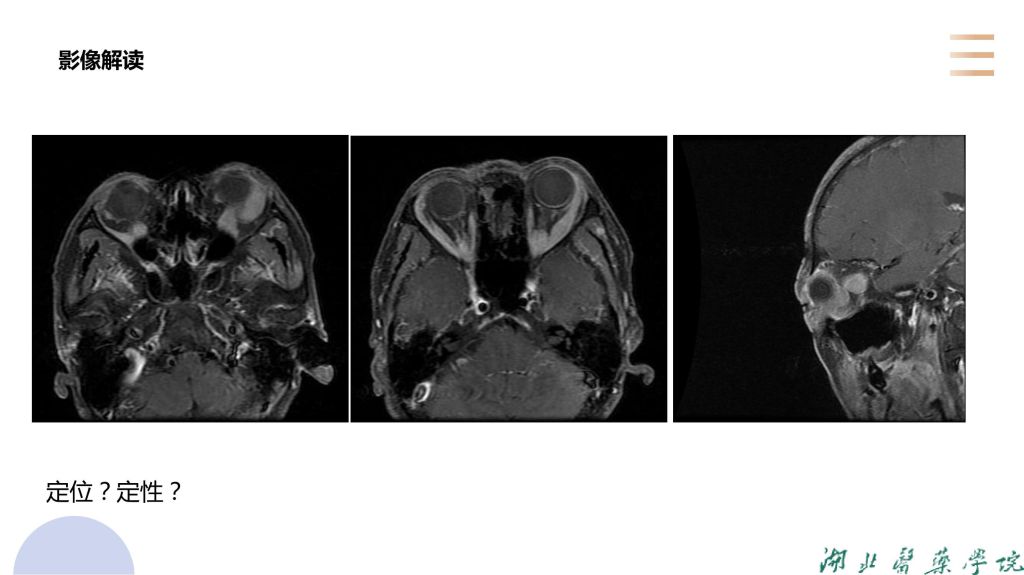

病例分析-眼眶淋巴瘤